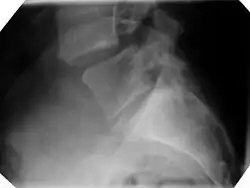

Bild 1: Gleiten zwischen Lendenwirbeln 4/5, im seitlichen Röntgenbild. -

Bild 1 ist die konventionelle Röntgenaufnahme eines Wirbelgleitens zwischen den Wirbeln 4 und 5 der Lendenwirbelsäule. Der Schweregrad liegt auf der Grenze zwischen dem Stadium 1 und 2. Rechts im Bild zeigt sich auch die knöcherne Unterbrechung des Wirbelbogens (Spondylolyse). Es handelt sich also um eine "richtige" Spondylolisthese (auch Spondylolisthesis vera genannt).